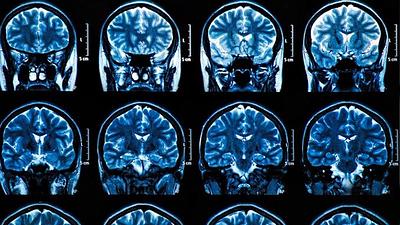

Exame de sangue pode detectar Alzheimer antes de primeiros sintomas

23/01/2019, 07:51

Desenvolvido por pesquisadores alemães e americanos, teste identifica no sangue proteína gerada na morte das células nervosas, até 16 anos antes do aparecimento da doença.